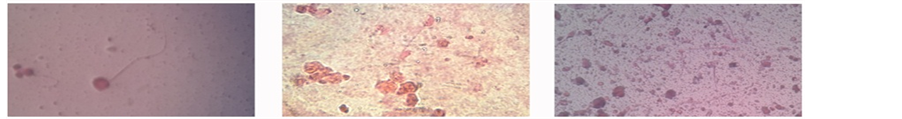

This indicates that plants constitute an important part of the primary healthcare system in developing world [16] . In our study, At the end of the experiment, the obtained sperms shapes were as below: In mice treated with Salvadora persica leaf extract as shown in Figure 1, at concentration 0.5% and 1.0%, normal sperms, while in 1.5%, circular head and short tail. Two tails attached to one head in 2.0%. At 0.5% and 1.0% of mice treated with Moringa pergrina leaf extract exhibited normal sperms whereas ecircular head and short tail obtained in

1.5%. And very long tail and circular head of sperms at 2.0% as it was administrated in Figure 2. In mice treated with Citrullus colocynthis seed extract, the sperms at 0.5% and 1.0 were normal. While at 1.5%, two heads attached to one tail and small, circular head attached to long tail at 2.0% as in Figure 3. The effect was dose dependant, that is the higher the dose the greater the effect. The fact that the extract contained some pro- oxidants like flavonoids, saponnins, anthraquinones, alkaloids and terpenoid suggests that the administration of the extract at higher doses of 100 - 1000 mg/kg body weight for two weeks may lead to oxidative damage due to free radical (FR) and reactive oxygen species (ROS) generation. The defect in sperm morphology detected in mice administered with the extract at higher doses demonstrated that the extract may have direct effect on sexual glands and sperm cells beside it pro-oxidant effect.

Figure 2. Observation of sperm shape and size of mice under the microscope treated with Moringa pergrinaat different concentrations (40´): (a) Control; (b) 0.5%; (c) 1.0%; (d) 1.5%; (e) 2.0%.